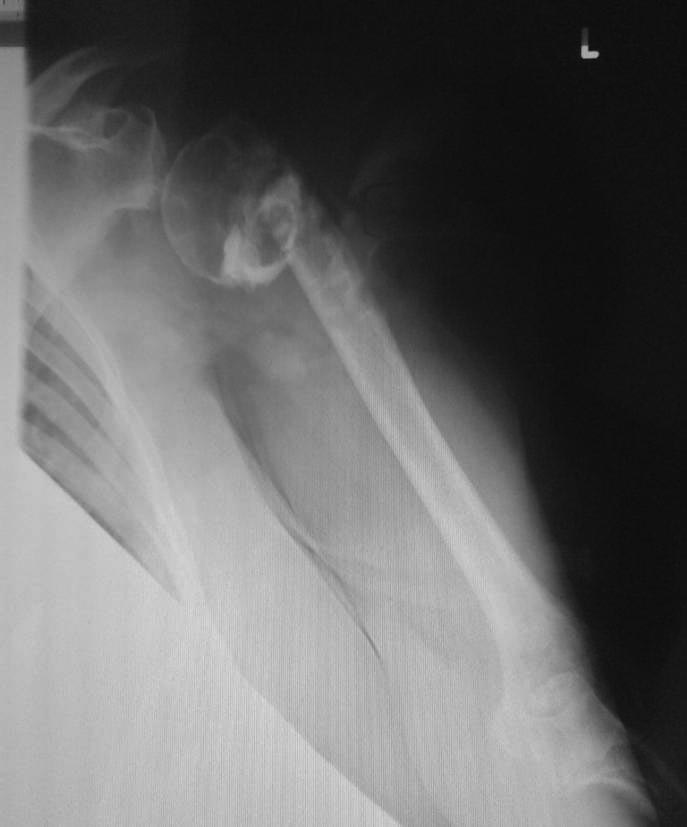

Доброго всем предпраздничного дня! Отправляю вам последний снимок моей пациентки. При удалении конструкции из руки было откачано много жидкости, пластинка и винты полностью выпали. Анализ на инфекции извлеченной жидкости не дал положительного результата. Перед следующей операцией кость должна была восстановиться. Прилагаю последний снимок. Какая перспектива, как думаете?

Одной проекции маловато для полноценного планирования, но в общих чертах - здесь хорошо бы выполнить закрытый интрамедуллярный остеосинтез современным стержнем для этой локализации.

Multiloc (Synthes) был бы IMHO наилучшим выбором, поскольку позволяет ввести максимальное количество винтов в головку. Но важнее имплантата - это хорошая репозиция. И лучше закрытая. Описание техники представлено здесь.

Пациентке предлагают только эндопротезирование. 7 винтов в головку кости были вкручены в точку. И от головки не осталось какого-то нормального фрагмента.

Все там не так плохо с головкой даже без аугментации. Главное, что цела манжета, то есть все мягкотканые прикрепления сохранены, то есть головка кровоснабжается. Кости там для фиксации специализированного гвоздя, в частности, Multiloc - более чем достаточно. Как сделать - в статье написано. Пусть доктора посмотрят, ничего там особо сложного нет.